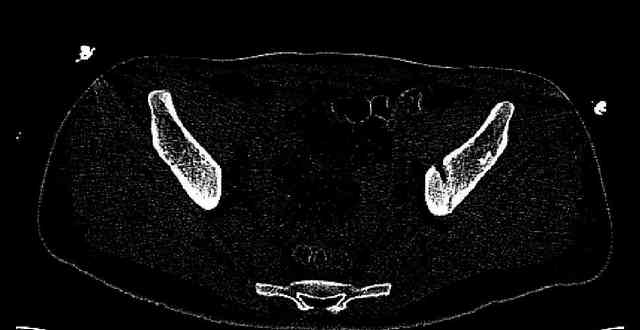

Some more images. Does it help to guess which part of the acetabulum is displaced?

Normal appearing SI joints and a healed posterior column limb... my bet's on caudal segment displacement.